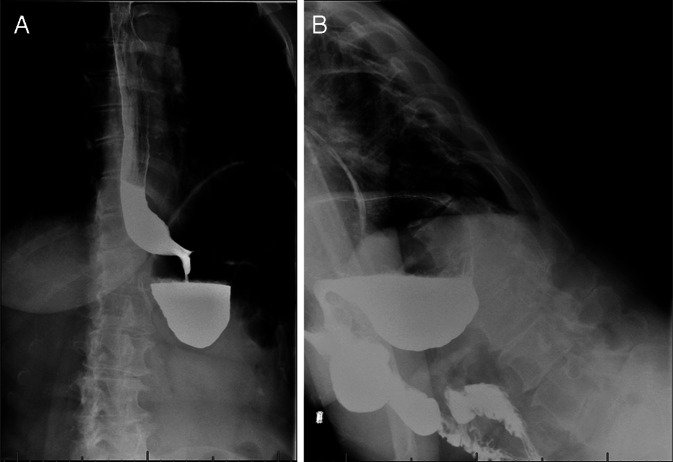

An Example of Cascade Stomach.